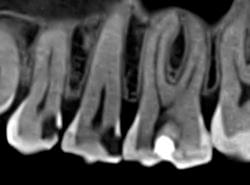

Ми розуміємо, наскільки важлива деталізація в ендодонтії та терапевтичному лікуванні.

Завдяки флагманському обладнанню PLANMECA, ми отримуємо знімки з мінімальним рівнем шумів та

високою роздільною здатністю, що дозволяє чітко візуалізувати морфологію кореневих каналів,

приховані каріозні порожнини та стан періапікальних тканин.